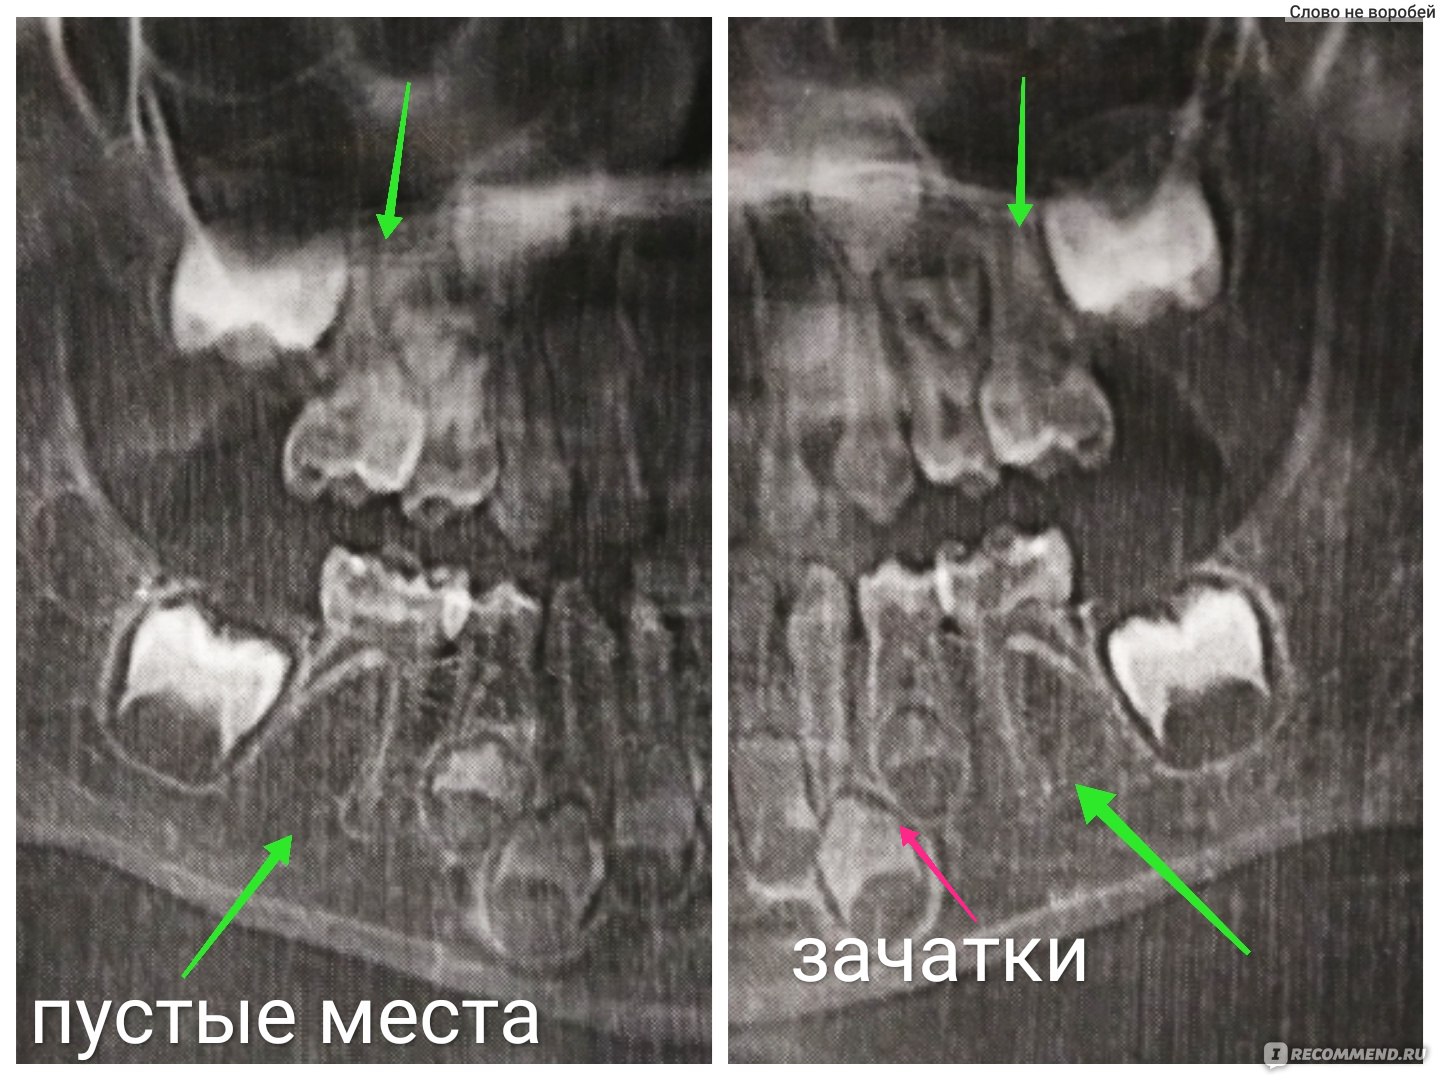

Стоматологические Исследования: Рентген Инвагинации Зубов